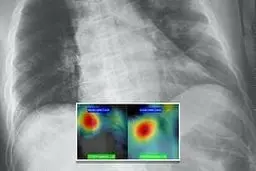

تشخیص "کروناویروس" با هوش مصنوعی با دقت ۹۸ درصد…

یکی از محققان آمریکایی موفق به تولید یک نرمافزار مبتنی بر…